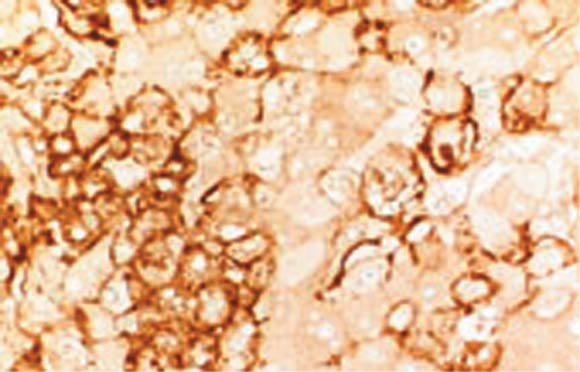

発症は突発的で進行も早い。潜伏期は2~21日で、汚染注射器を通した感染では早く、接触感染では長い。インフルエンザ様症状が進行し、重篤化する。発熱、頭痛が100%に、腹痛、咽頭痛、筋肉痛、胸部痛が80%に、出血(吐血、口腔歯肉、消化管)が70%にみられる。出血は死亡例の大部分でみられる。2000年のウガンダでの流行では上記症状に加えて、衰弱のほか下痢等の消化器症状が目立ち、出血症状は10%以下であった。肝臓でのウイルス増殖(図3)による肝腫脹により、右季肋部の圧痛や叩打痛が特徴的である。症状として“エボラ出血熱に特徴的なもの”はない。

図3.エボラウイルス実験感染サルの肝臓

肝細胞内に好酸性封入体がみられ(左)、免疫組織化学(右)でエボラウイルス抗原が認められる(Drs McCormick JB &Fisher- Hoch SPによる実験感染サル組織を用いて、抗エボラGP抗体でウイルス抗原を検出した)